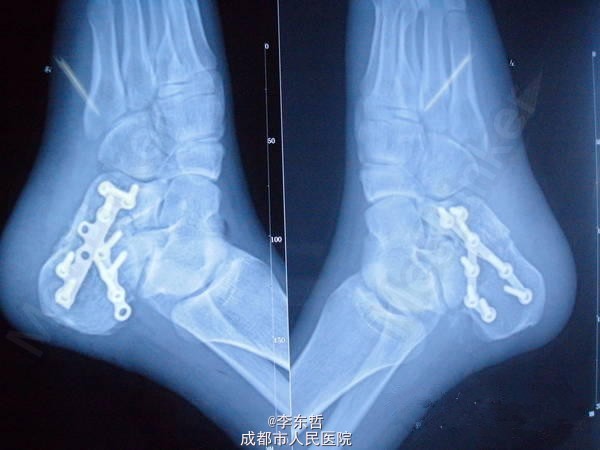

左足跟骨骨折

患者成年男性,车祸伤致左足根部骨折,疼痛肿胀不能活动半天入院,行急诊手术处理。